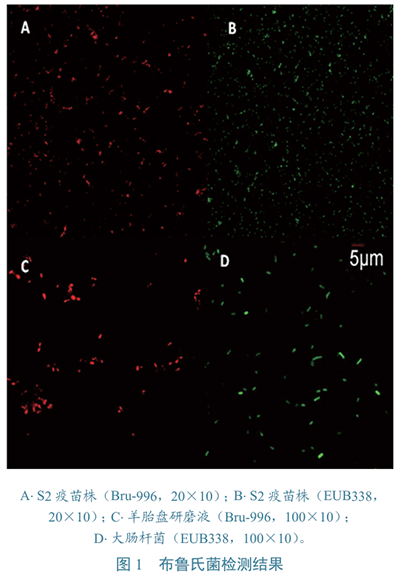

布魯氏菌???:雜交前,對布魯氏菌無需特別處理,45 ℃雜交1.5 h即出現紅色熒光信號,200倍放大下觀察,清晰可見(圖1-A、B)。雜交3 h可完全滿足檢測需要,延長時間至8 h或12 h,信號強度不會明顯增加,因而布魯氏菌熒光原位雜交簡便、快速,可在4 h內完成。Bru-996探針與布魯氏菌S2、A19、Rev.1疫苗株和HN6、XJ-1分離株,均產生雜交信號,在牛結核分枝桿菌、禽結核分枝桿菌和大腸桿菌中沒有觀察到熒光信號,表明該探針具有較高的特異性。從5個已知布魯氏菌病羊組織病料(2個肝臟、2個脾臟、1個胎盤)中均成功檢測到布魯氏菌(圖1-C),證明該方法具有較高的敏感性。在高倍放大下觀察,布魯氏菌呈短桿菌,小于大腸桿菌(圖1-D)。